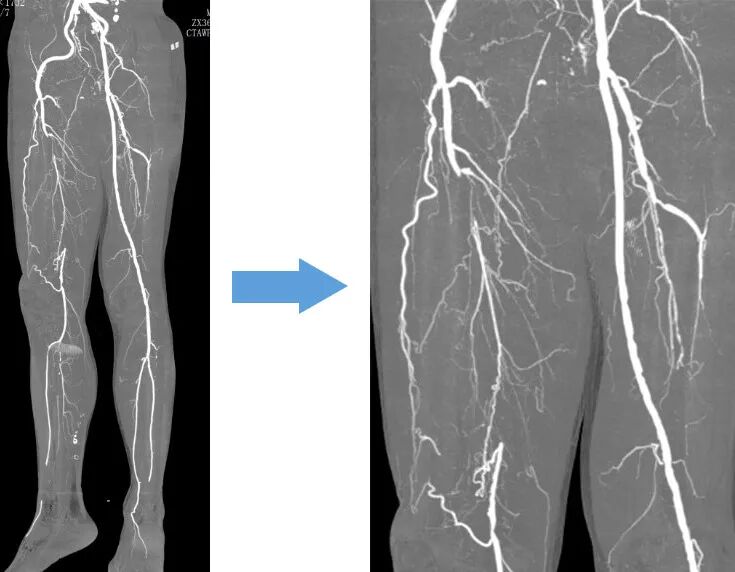

术前双下肢CTA特征:

1、右股浅动脉长段闭塞(股浅起始段开始)

2、右股浅远端部分侧枝代偿至腘动脉(提示慢性闭塞为主)

3、右股深动脉主干中段未显影(不排除栓塞可能)

医疗组再次调阅术前CTA影像横断面:右股浅近端此区域存在血管扩张样改变(见下图)